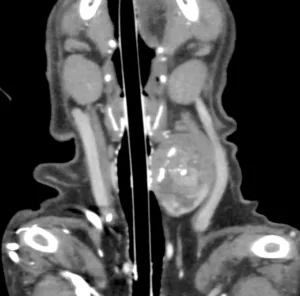

軟部組織肉腫

右前肢背側の皮下腫瘤

やや硬いが、可動性あり

組織生検を実施して、軟部組織肉腫と診断

その後に外科摘出を行なった